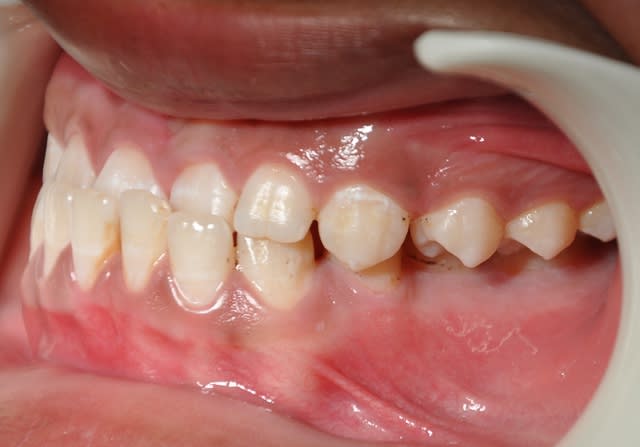

comment on peut traiter cet articulé gauche

Concernant l’occlusion croisée à gauche, il y a deux problèmes : un problème vertical d’égression à partir des canines et un problème transversal.

Corrige d'abord le problème vertical, l’occlusion croisée sera ensuite relativement facile à traiter avec de simples élastiques.